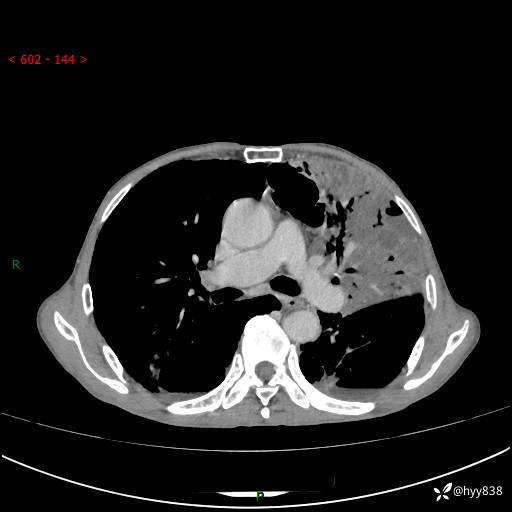

老年男性,反复咳嗽、咳痰、气喘10余年,再发3天。大叶性实变+胸膜病变-结果公布

胸部CT平扫+增强